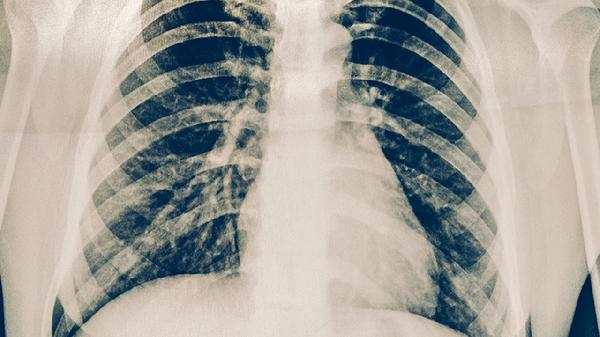

肺部感染或结核累及胸膜时会出现呼吸相关性胸痛,可伴有低热、咳嗽症状。需进行胸部CT检查明确病因,细菌性感染需使用注射用头孢曲松钠等抗生素治疗,结核性胸膜炎应规范服用异烟肼片等抗结核药物。急性期建议卧床休息并监测血氧饱和度。